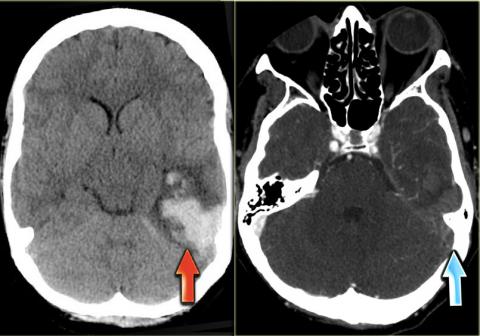

در تصاوير سمت چپ بيمار مبتلا به انفارکتوس هموراژيک در لوب تمپورال (فلش قرمز) است

به سينوس عرضي متراکم به دليل ترومبوز (فلش هاي آبي) توجه کنيد